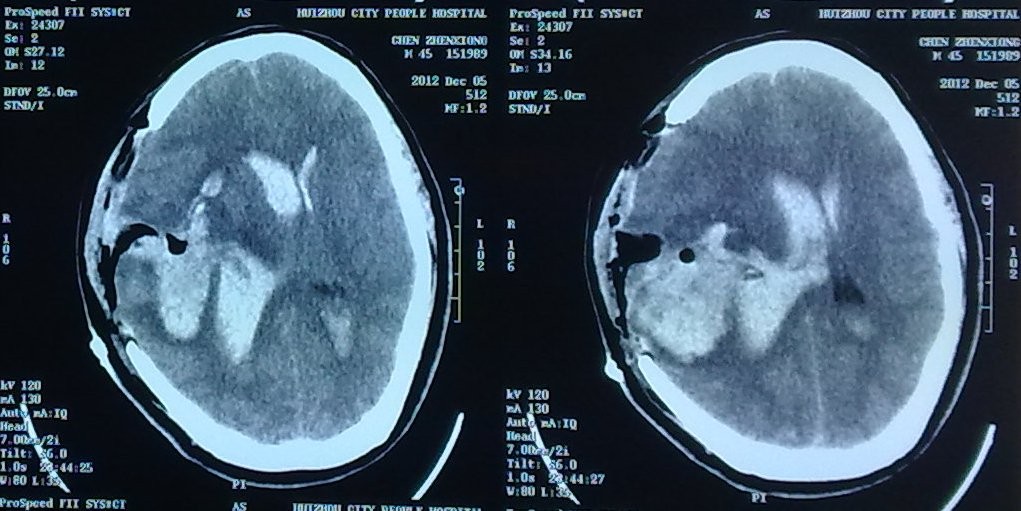

這次,我們使用顯微鏡進(jìn)行顯微手術(shù),以期徹底清除血腫并切除AVM病灶。我院這臺手術(shù)顯微鏡是當(dāng)前國際主流品牌“蔡司NC4高級顯微鏡。余永強(qiáng)主任主,采用當(dāng)前最先進(jìn)微創(chuàng)技術(shù)理念“無腦壓板微創(chuàng)技術(shù)”在顯微鏡下單純利用一個吸引器和一個雙極電凝進(jìn)行操作,并不需要腦壓板的牽拉,以盡量減少損傷。術(shù)中利用這兩個工具互相配合,借助顯微鏡的良好照明及清晰成像系統(tǒng),清楚顯露術(shù)野,完全清除腦內(nèi)血腫,并開放側(cè)腦室清除腦室內(nèi)血腫,取得滿意止血效果。憑借沉穩(wěn)、鎮(zhèn)定、嫻熟的顯微手術(shù)技巧,我們進(jìn)一步深入探查找到了出血動靜脈畸形團(tuán),在顯微鏡下清楚地分離出AVM的供血動脈及引流靜脈,完全切除血管畸形團(tuán)。由于顯微手術(shù)操作輕柔微創(chuàng),無腦壓板牽拉損傷,手術(shù)繼發(fā)損傷小,盡量保存了腦組織,最終挽救了病人的生命。

2、顯微手術(shù)完全清除血腫。

3、顯微手術(shù)。